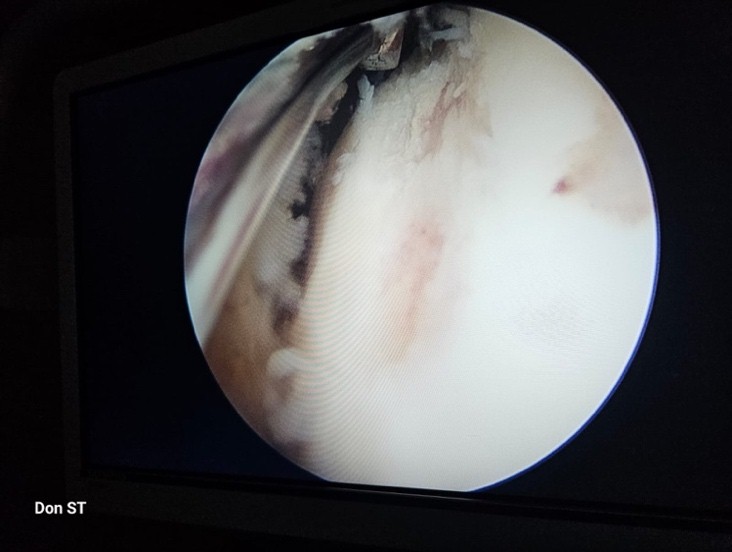

The procedure was performed under spinal anesthesia, in a supine position. Hip traction was applied. Antibiotic (Injection Cefuroxime 1.5 g) administered before skin incision. An anterolateral portal was established under C-arm guidance. Modified anterior portal established under direct vision. Diagnostic hip arthroscopy was performed, revealing a focal osteochondral defect of size 15 mm × 5 mm located over the weight-bearing superoanterior dome of the femoral head (Fig. 4). The acetabulum and labrum were normal.

Figure 4: Arthroscopic image showing the chondral defect.